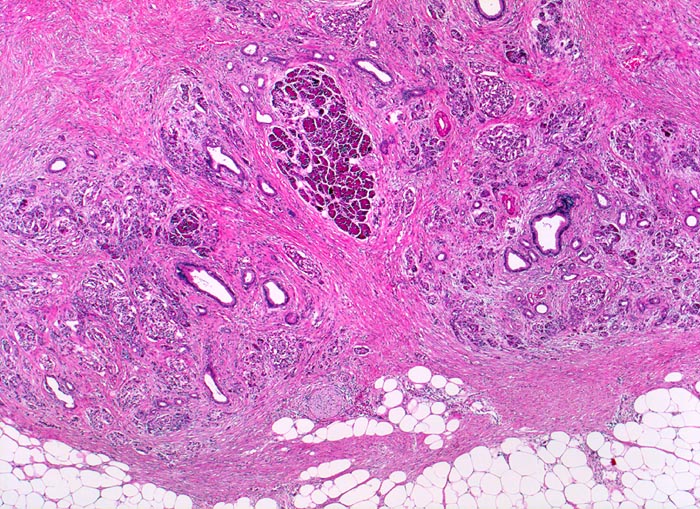

Je nach Ursache der chronischen Pankreatitis unterscheidet sich das Muster der Fibrose. Die Nekrosen des interlobulären Gewebes und der interlobulären Gänge bei ethylischen Pankreatitisschüben führen primär zu einer interlobulären Fibrose und interlobulären Gangstrikturen. In den betroffenen interlobulären Gängen führt der Sekretstau zur Konkrementbildung (verkalkte Proteinpräzipitate). Wie bei einer chronisch obstruktiven Pankreatitis kommt es in den unvollständig drainierten Läppchen zu einer Atrophie der Azini verbunden mit intralobulärer Fibrose. Letztere Areale enthalten schliesslich nur noch Reste unregelmässig verteilter Gänge, Inseln, Nerven und Gefässe. In vielen Fällen lassen sich extrapankreatische Pseudozysten gefüllt mit nekrotisch-hämorrhagischem Detritus in der Nachbarschaft der fibrosierten Bezirke nachweisen. Ein Tumor (> 2066), eine Narbe oder einen Stein können als Folge einer Obstruktion des Pankreasganges im Pankreaskopf eine diffuse Atrophie und Fibrose des Pankreas nach sich ziehen. Diese Form wird als chronische obstruktive Pankreatitis bezeichnet und ist gekennzeichnet durch eine deutliche poststenotische Dilatation des betroffenen Pankreasganges ohne Konkrementbildung und eine diffuse Fibrose des an den obstruierten Gang angrenzenden Parenchyms. Bei einer Schädigung des Gangepithels und der Gangwände wie bei hereditärer oder Autoimmunpankreatitis entwickelt sich primär eine periduktale Fibrose. Im Gegensatz zum duktalen Adenokarzinom ist das erhaltene Parenchym bei der chronischen Pankreatitis lobulär angeordnet. Drüsenepithelien zeigen keine Atypien. Karzinomverdächtig sind irregulär infiltrierende atypische Drüsen, atypische Drüsen in unmittelbarer Nachbarschaft von grösseren Gefässen ohne dazwischenliegende Azini, Perineuralscheideninvasion, rupturierte oder inkomplette Drüsen, und Drüsen mit luminalem nekrotischem Detritus.

• Erhaltene Läppchenarchitektur.

• Breite Bänder von sklerosiertem zellarmem Bindegewebe verlaufen zwischen den Läppchen.

• Atrophie des exokrinen Pankreas.

• Erhaltene Inseln und Gangstrukturen.

• Spärliches chronisches Entzündungsinfiltrat.

• Rechts oben ist eine partiell vom Rand her durch Granulationsgewebe organisierte lytische Fettgewebsnekrose erkennbar. Diese ist Folge eines akuten pankreatitischen Schubs.